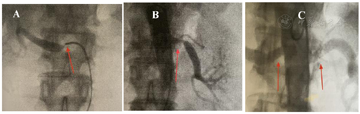

根据患者诊疗经过和此次入院后全主动脉血管造影结果,诊断大动脉炎?入院后给予"拜新同30 mg Bid、氢氯噻嗪12.5 mg qd、美托洛尔缓释片90 mg qd、硝普钠(根据血压调整剂量)、阿托伐他汀钙40 mg qd"治疗,血压持续维持在170/90 mmHg。于2021-4-25行肠系膜上动脉、双肾动脉、腹主动脉选择性造影,结果提示:肠系膜上动脉开口狭窄99%、左肾动脉开口狭窄90%、腹主动脉溃疡(图3)。遂于肠系膜上动脉植入支架、腹主动脉覆膜支架(反复球囊扩张肠系膜上动脉残余狭窄大于80%,且腹主动脉覆膜支架可能导致肠系膜下动脉闭塞导致肠缺血)、左侧肾动脉支架内球囊扩张,残余狭窄小于50%。术后给予患者"拜新同30 mg qd、美托洛尔缓释片90 mg qd、阿司匹林100 mg qd、替格瑞洛90 mg Bid、阿托伐他汀20 mg qd",血压降至110~-120/70 mmHg。术后第2天(2021-4-26)患者开始出现间断发热,体温波动于37.0~38.4℃,无畏寒、寒战,发热期间患者无鼻塞流涕、无咳嗽咳痰、无腹痛腹泻症状,食欲及精神状况良好。查炎症指标:最高白细胞14.8×109/L、血沉69 mm/h、超敏C反应蛋白11.6 mg/L,期间5次血培养、尿培养均未见细菌生长。病毒抗体系列、降钙素原、真菌D-葡萄糖检测、曲霉半乳甘露聚糖检测等均未见异常,经给予"退热、哌拉西林舒巴坦"治疗,于术后第6天(2021-4-30)体温降至正常。治疗期间风湿免疫科会诊,根据1990年TA分类诊断标准:患者小于40岁发病,经影像学检查发现主动脉及分支血管狭窄,满足TA的准入条件且分类标准得分≥5分,故诊断TA。加用醋酸泼尼松60 mg qd、环磷酰胺100 mg qd。出院后风湿免疫科、心内科共同随诊,随访中患者血压维持在120~135/70~90 mmHg,术后5个月复查全主动脉血管强化CT提示:肠系膜上动脉+双肾动脉+腹主动脉支架通畅,余其他受累血管病变未见进展。